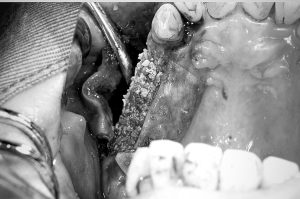

④人工骨を補填

インプラントが露出していた部分に、人工骨を補填した状態。

骨の幅、高さが不足している部分を過不足ないように調整する。